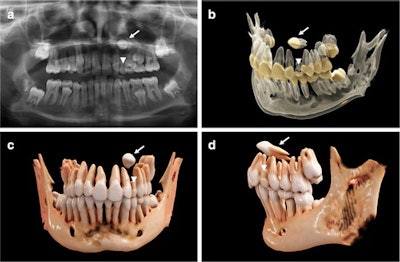

An 11-year-old girl with a horizontally impacted canine (white arrows) and a persisting deciduous canine (white arrowheads). (a) An x-ray of the girl’s mouth. (b) Semitransparent reconstruction parameters are used to visualize bone, teeth, and different dental tissues. (c and d) The teeth and bone tissue with a soft kernel show a photorealistic visualization in both a frontal and lateral view.